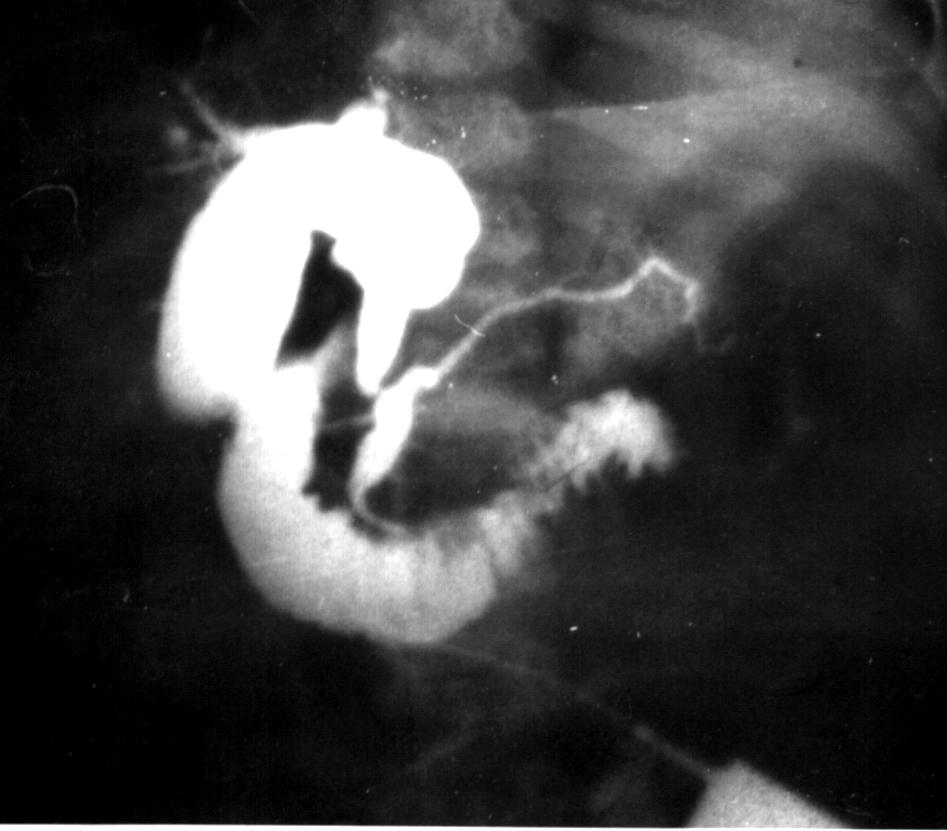

Cbd5.jpg (58933 bytes)